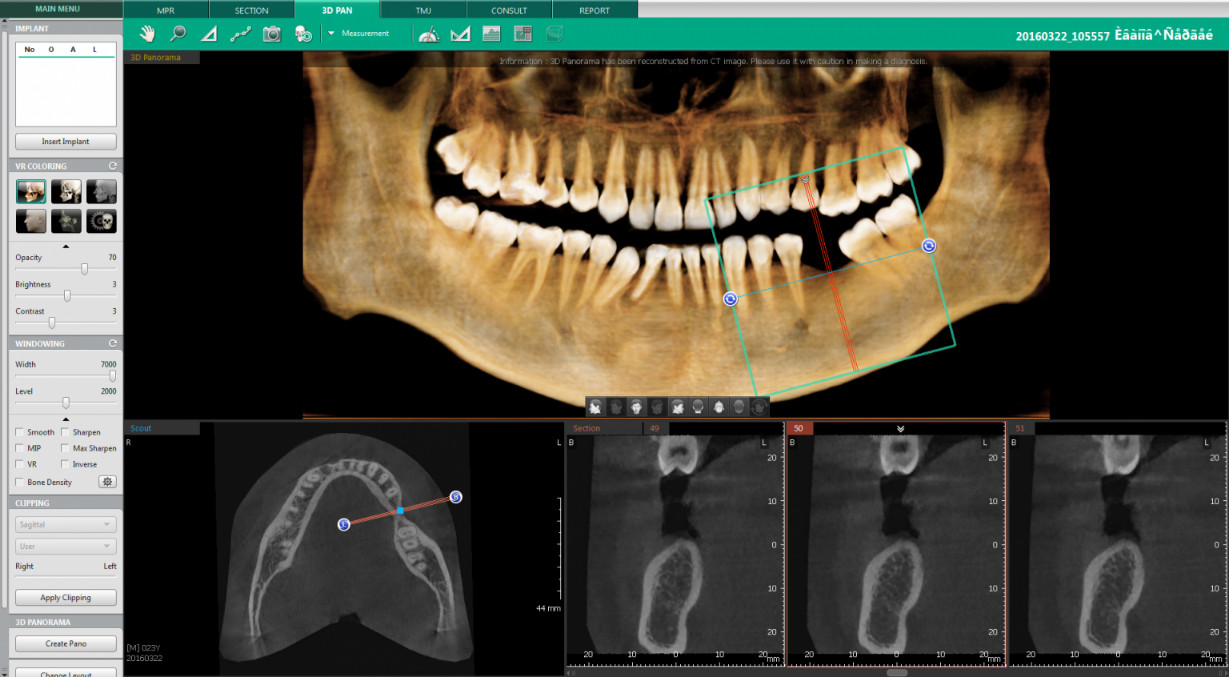

Протокол планирования дентальной имплантации по данным КЛКТ

Многофункциональное программное обеспечение. Обучение работе с ведущими программами для КЛКТ, такими как Ez3D, Romexis Viewer, OnDemand3D, и Galileos, что расширяет возможности анализа и планирования дентальной имплантации.

Точная диагностика и планирование. Умение точно определять размеры и типы костной ткани для выбора оптимальных имплантатов, что повышает успех и долговечность имплантационных процедур.

Снижение необходимости повторных исследований. Способность работать с различными интерфейсами КТ-снимков позволяет избежать отправки пациентов на повторные исследования, независимо от используемого ПО.

Освоить методы планирования дентальной имплантации с использованием данных КЛКТ и различных программ, что позволит стоматологам-хирургам проводить имплантацию с высокой точностью и эффективностью.

• Базовые принципы по планированию дентальной имплантации. Определение объема и типа кости. Первичная оценка данных для подбора типа и размера имплантата.

• Пошаговый протокол планирования дентальной имплантации в Ez3D (Vatech). Как перенести полученные данные интраоперационно.

• Алгоритм работы с программой Romexis Viewer (Planmeca). Планирование дентальной имплантации. Особенности и нюансы.

• OnDemand3D (KAVO). Виртуальное позиционирование дентальных имплантатов. Тонкости работы с программой.

• Протокол планирования дентальной имплантации в Galileos (Sirona).